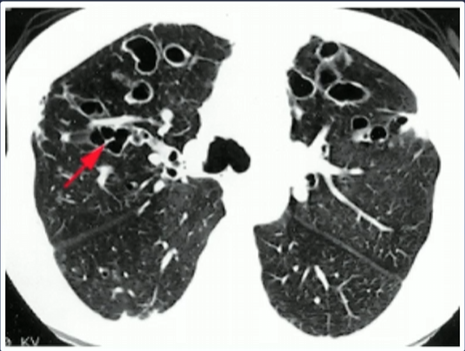

Qual o quadro clínico da bronquiectasia?

• Tosse maioria dias da semana

• Expectoração mucopurulenta e tenaz por meses a anos + exacerbações

• Queixas menos específicas: dispneia, hemoptise, sibilância e dor torácica pleurítica